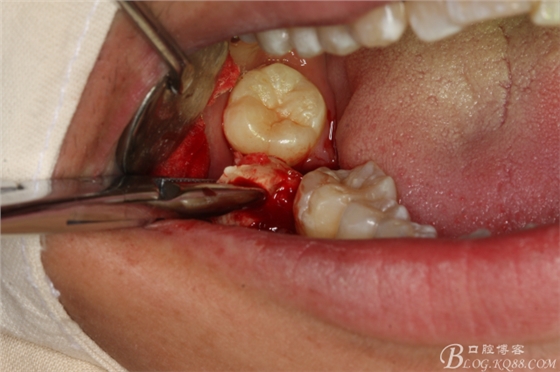

圖7.不切開(kāi)、不翻瓣、利用有限空間直接高速牙鉆分牙

圖8.先橫斷47牙冠,盡量從牙頸部橫斷

圖9.潛掘法橫斷牙冠